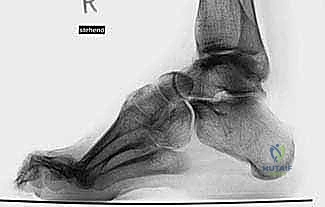

الشكل 1 • تشوهات القدم الجوفاء، منظر جانبي. لاحظ زيادة الانثناء الأخمصي لمقدمة ومنتصف القدم بالنسبة لمؤخرة القدم، وهو ما يسبب ضغطًا هائلاً على مشط القدم.